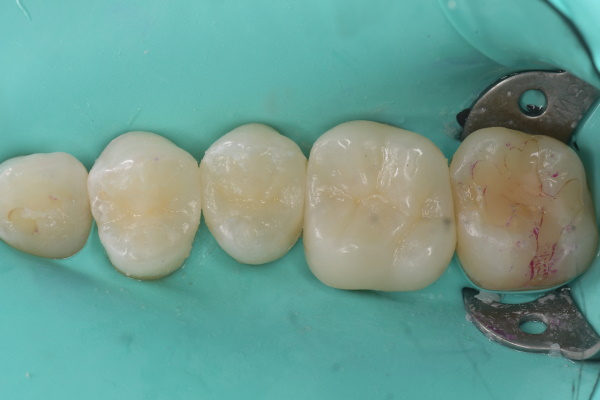

セラミック治療の治療例です。虫歯になった歯を、見た目もきれいに治したいとのご希望で来院されました。当院にて、3本同時にセラミックによる修復を実施しました。染め出しにより取り残しや汚れを確認し、プラークなどを除去したうえでセラミックを装着しています。オキシガードは、過酸化物と還元剤による化学重合反応により、歯科接着用レジンセメント表面の未重合層を硬化させる材料です。さらに、未重合層を空気から遮断することで確実な硬化を促します。接着効率をあげるためにラバーダムを使用し治療を行っております。

セット後